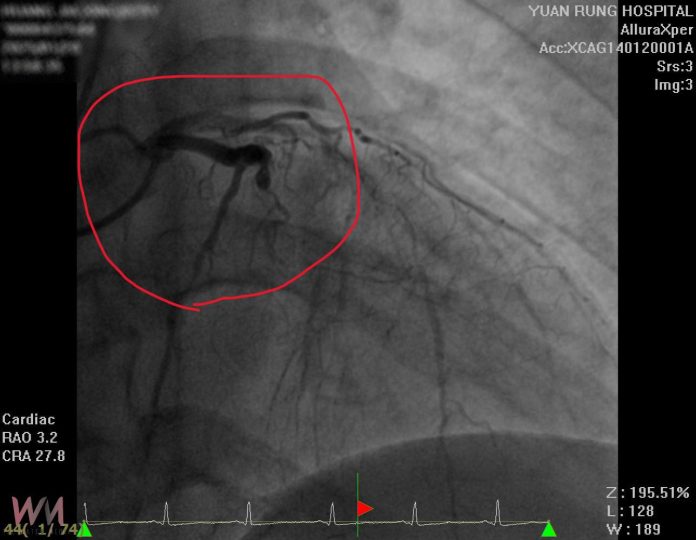

陳醫師表示,原本認為29歲的男子罹患血管問題的機率較低,但檢查結果顯示,患者的三條主要血管左前降支、左迴旋支及右冠狀動脈均嚴重阻塞,這也是導致心臟功能衰退的主因。不同於因病毒感染而引發的心臟衰竭,這名男子的情況是由慢性血管阻塞所致。該男子過去曾因高血壓未治療、熬夜和不良飲食習慣,導致血管逐漸狹窄,最終造成心臟功能衰退。